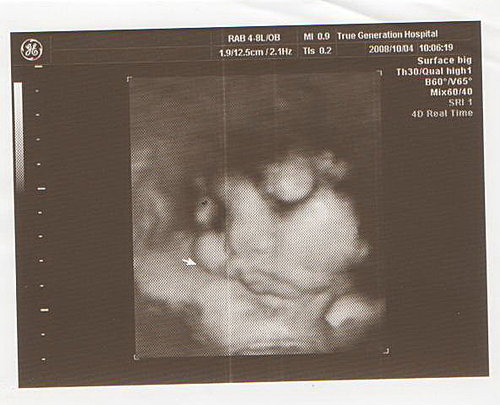

轉4D時

由於寶寶側臉

所以看不到正面

可是看到臍帶繞了脖子一圈

醫生說沒有辦法判斷是緊還是鬆

因此要多留意胎動

下次產檢10月4日